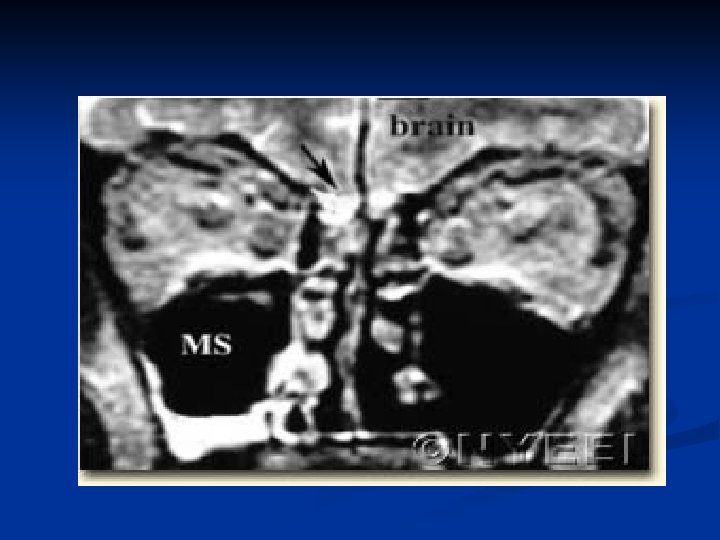

Demonstrate the Cause Over ½ the cases of nontraumatic rhinorrhea are high pressure leaks, majority related to intracranial tumours. n CT scans and MRI have their diagnostic role n

Localization of the leak Radiology plays the key role to see the anatomical site, size, side of the fistula n Bone defects, air fluid levels and erosions can be seen. n Plain X rays… Pneumocephalus/ air fluid levels n CT scan in axial/ coronal views… Skull Base #s, CSF fistulae n MRI… is not used as it is unable to show bone windows n